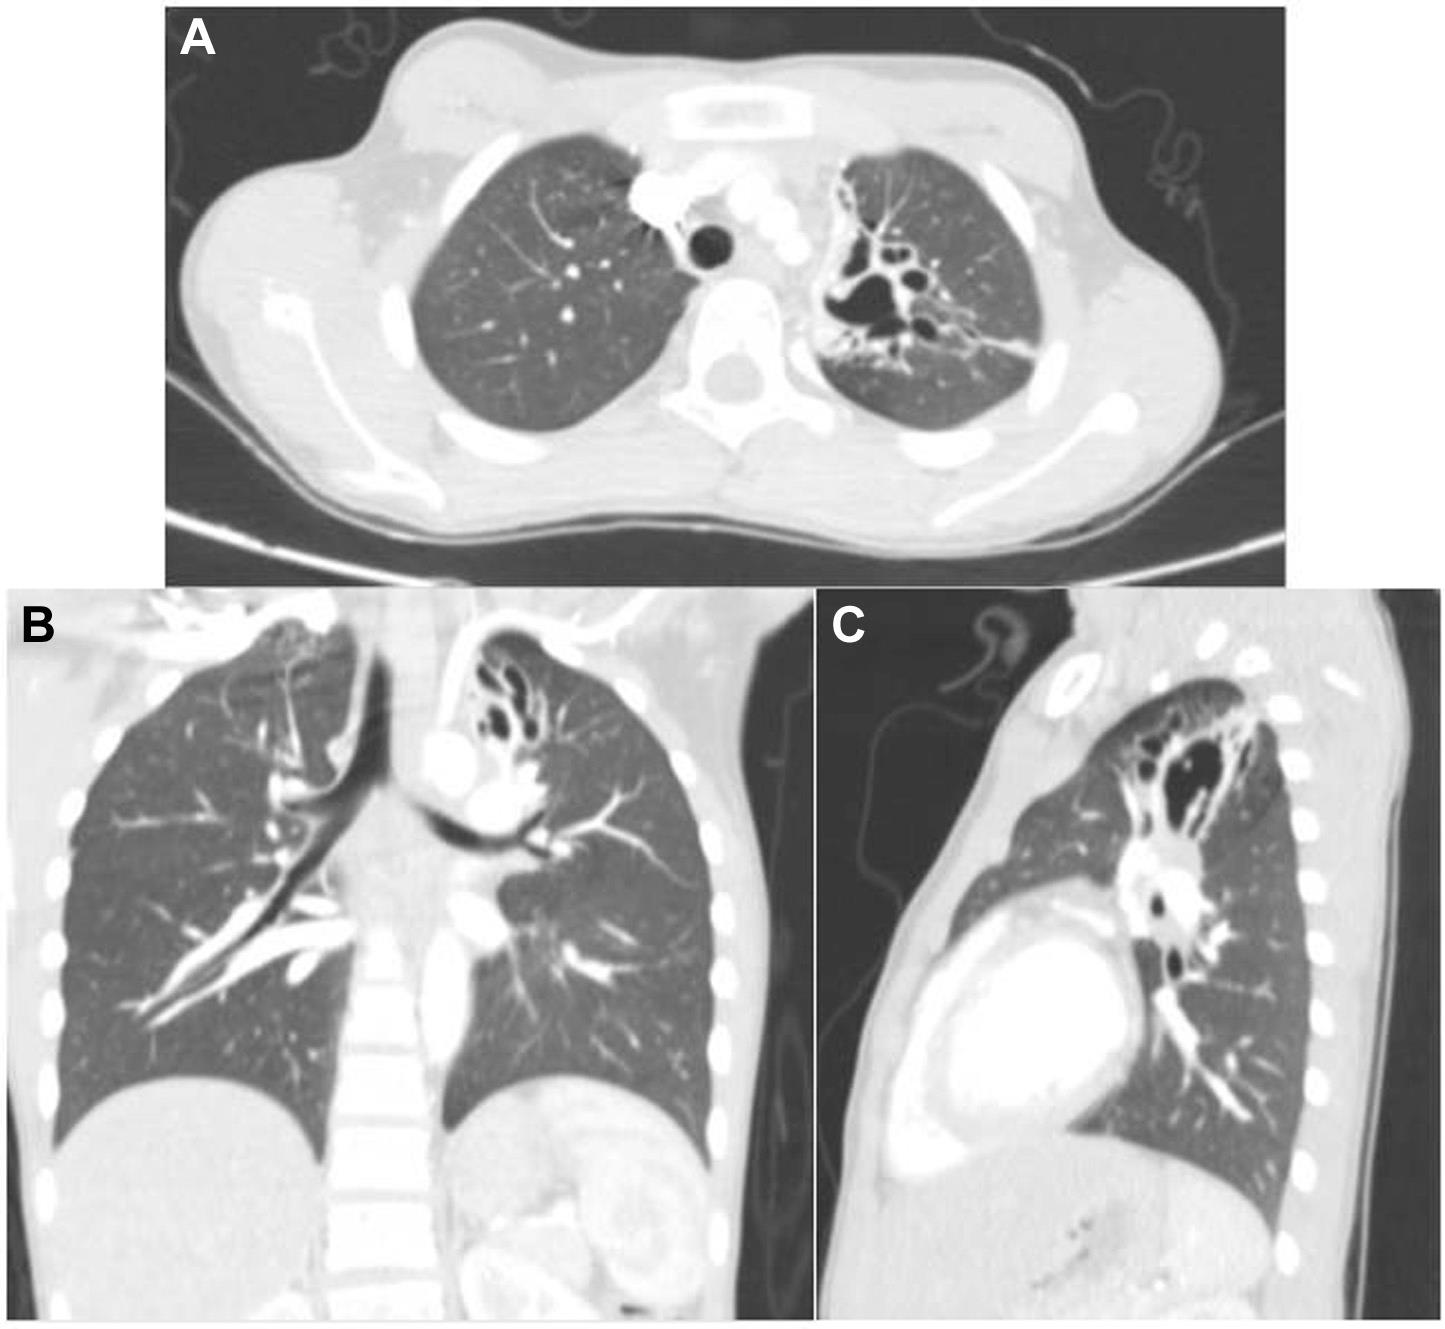

HRCT显示左肺上叶有一个大而不规则的实质炎症突起,边缘呈小叶状。突起内有囊性和空洞性病变,周围有几个卫星结节,通向左上叶的支气管略狭窄,但左主支气管正常(图2)。腹部超声检查正常,结核分枝杆菌纯化蛋白衍生物试验阴性。包虫病血清学检查(酶联免疫吸附试验

)阴性。

图2 胸部CT显示左上叶肺内有一大片不规则的实质炎性突起,边缘呈小叶状。

(A).横断面 (B).冠状面 (C).左腋下矢状面 突起内可见囊性和空洞性病变,通向左上叶的支气管变窄。